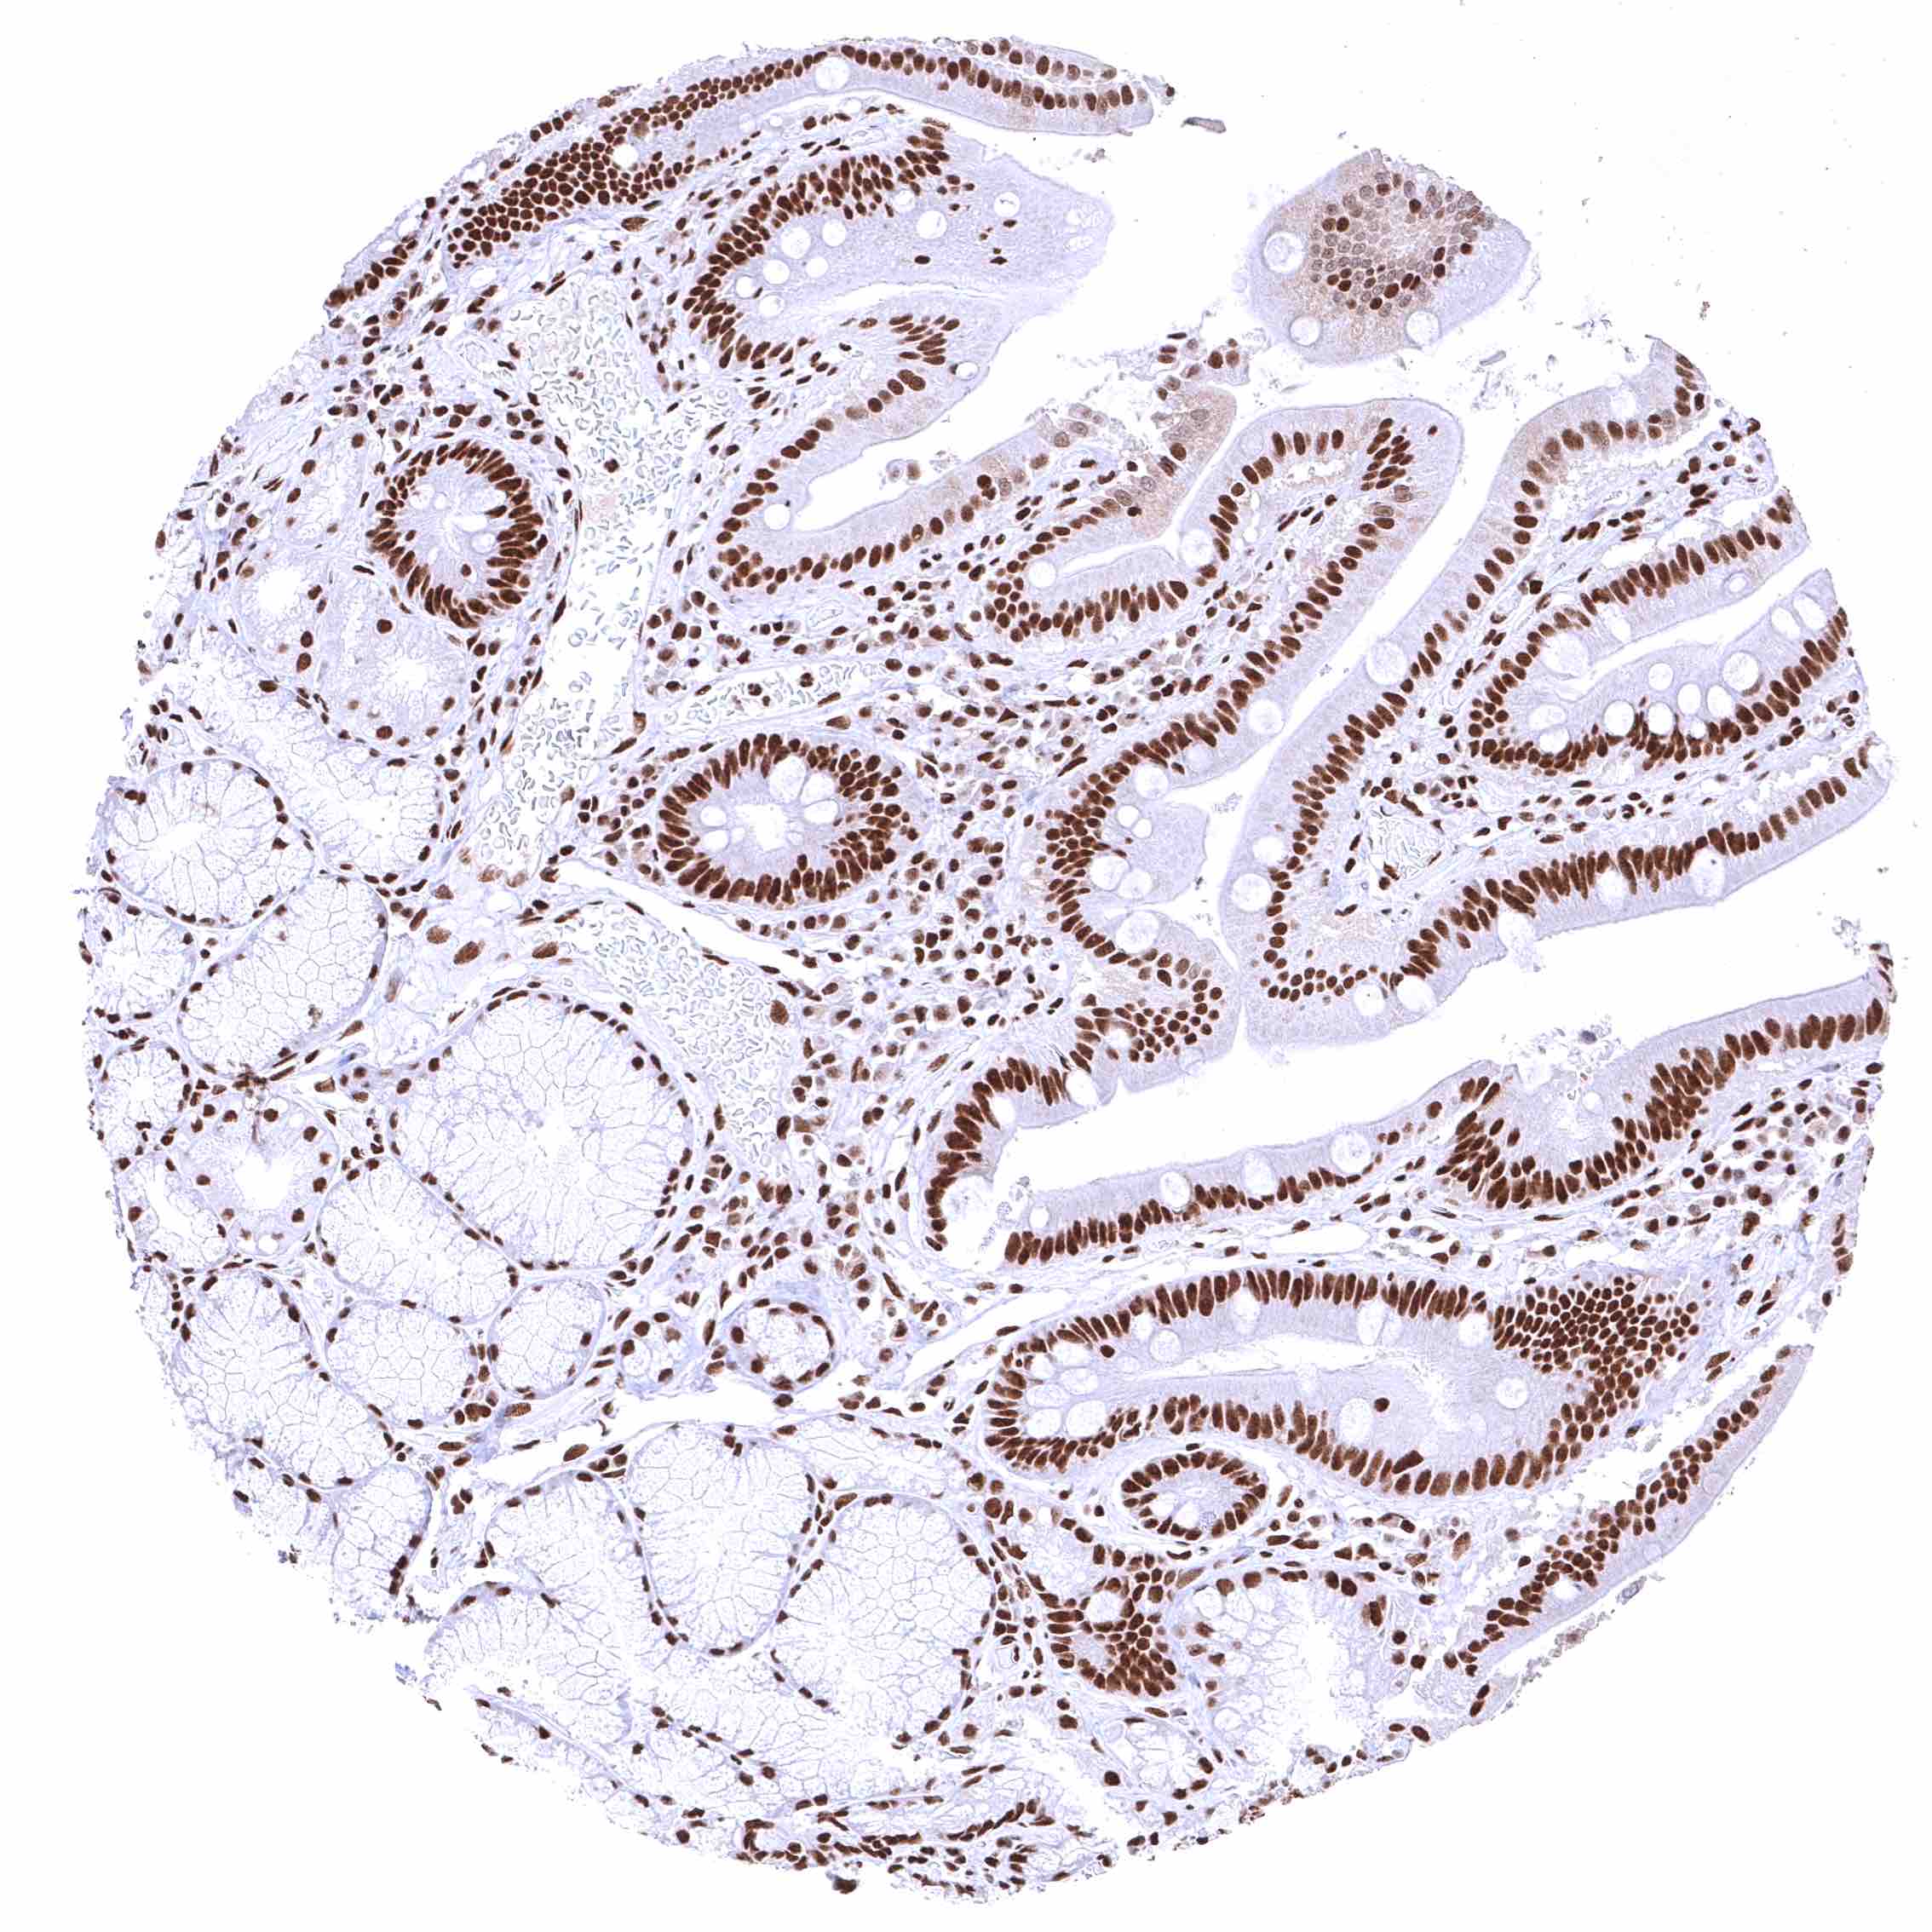

Duodenum, mucosa – BRD4 staining of surface epithelial cells is markedly stronger than in Brunner glands.